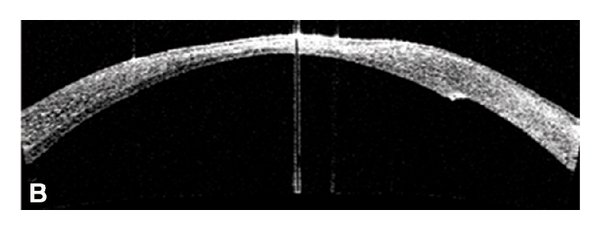

At postoperative day 1 the lenticule was attached, the anterior chamber was formed, and intraocular pressure was normal (Figure 1). Eye patch was placed and moxifloxacin 1% (Vigamoxi, Alcon laboratories, Fort Worth Texas, EU) and prednisolone acetate 1% (Prednefrin, Allergan, Los Angeles, CA, USA) were instilled QID. Lubrication with unpreserved Sodium Hyaluronate (Lagricel Sophia laboratories, Guadalajara, Mexico) was continued every hour. Pressure patch was placed and the patient was examined in the clinic every 72 hours for the next 14 days.

At 1 month postoperatively the graft was still well adhered, but a 4.00 mm persistent epithelial defect was present with no signs of epithelial healing. A multilayer amniotic membrane graft using cryopreserved amniotic membrane (AMNIOCV; Instituto de Oftalmologia “Conde de Valenciana” IAP, Mexico City, Mexico) was then performed and sutured with 10-0 nylon. The ocular surface healed quickly and an epithelial healing occurred over a 2-week period (Figure 2). The sutures were removed and the topical medications reduced to unpreserved sodium hyaluronate (Lagricel Sophia) five to six times a day and topical and prednisolone acetate 1% (Allergan) QID and tapered over the next 4 months.

Eight months after the procedure the patient had a stable and healthy ocular surface with adequate corneal integrity (Figure 3). Penetrating keratoplasty to restore optical properties of the cornea and to promote visual rehabilitation is considered for the near future.